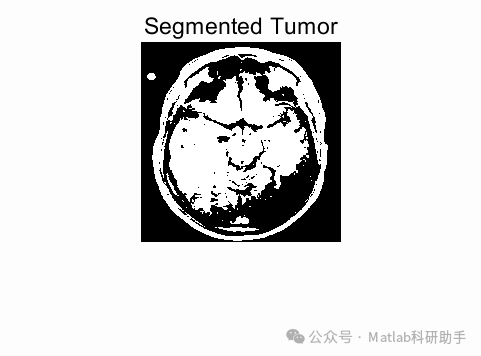

⛳️ 运行结果